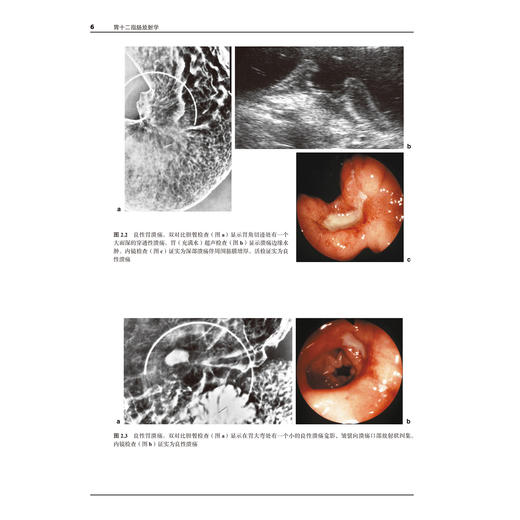

本书由英国剑桥大学医学院A.H.Freeman先生和E.Sala女士主编,是一部基于多学科诊治框架的胃十二指肠放射学专著。该书对胃、十二指肠疾的解剖、生理、病理、内镜、超声内镜、钡餐造影、CT、磁共振成像、同位素检查和介入放射学等方面进行了系统、深入的阐述,并结合具体案例对重要的临床问题进行剖析和总结。本书由中山大学附属第五医院张亚琴教授、暨南大学附属华侨医院史长征教授、江门中心医院崔恩铭教授和南方医科大学南方医院吴元魁教授共同主持和消化内科、胃肠外科、血管介入、核医学科、影像科医师参与,历经3年对原著进行了翻译。是一部这是一部具有很高学术价值而且实用性很强的专著。

结合具体案例对胃、十二指肠疾的解剖、生理、病理、内镜、超声内镜、钡餐造影、CT、磁共振成像、同位素检查和介入放射学等方面进行系统、深入的阐述